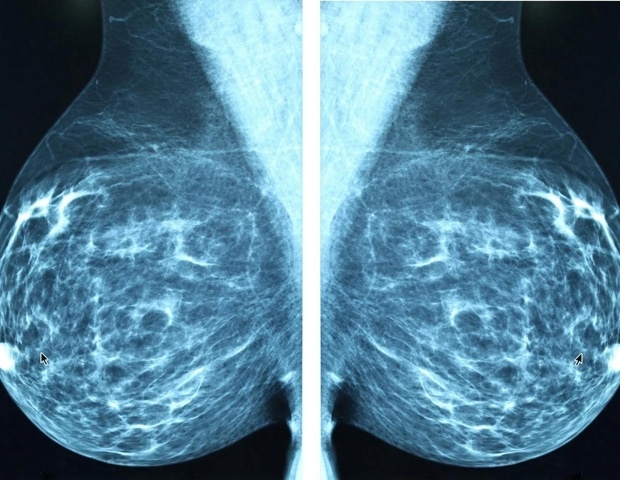

Η αναγνώριση μεταστατικών κυττάρων σε πρωτογενείς όγκους μαστού

Η κατανόηση του ποιες κυτταρικές ομάδες μέσα σε έναν όγκο θα προχωρήσουν στη δημιουργία μεταστάσεων παραμένει μία από τις πιο μεγάλες προκλήσεις στην έρευνα κατά του καρκίνου. Μία πρόσφατη μελέτη, με επικεφαλής την ομάδα Cell Plasticity in Development and Disease της Άνγκελα Νιέτο στο Ινστιτούτο Νευροεπιστημών, παρέχει μια απροσδόκητη απάντηση: οι κυτταρικές ομάδες που θα δώσουν προέλευση σε μεταστάσεις μπορούν ήδη να εντοπιστούν μέσα στον πρωτογενή όγκο.

Για την επίτευξη αυτών των συμπερασμάτων, η ομάδα χρησιμοποίησε πειραματικά μοντέλα ποντικών, αναλύσεις μεμονωμένων κυττάρων, μελέτες χρωματίνης και τεχνικές χωρικής μεταγραφικής αναλύσεως που επιτρέπουν την απευθείας παρατήρηση της οργάνωσης και της συμπεριφοράς των κυττάρων εντός του ιστού του όγκου. Οι ευρηματικές παρατηρήσεις από χιλιάδες κύτταρα αναλύθηκαν από τον βιοπληροφορικό εμπειρογνώμονα της ομάδας. Οι αναλύσεις δειγμάτων ασθενών με καρκίνο μαστού ενδέχεται να διαδραματίσουν ακόμη πιο καθοριστικό ρόλο στην πρόβλεψη του κινδύνου μετάστασης, εφόσον ανιχνευθούν παρόμοια πρότυπα έκφρασης του Prrx1, γεγονός που επηρεάζει την ταξινόμηση των όγκων και τις κλινικές προβλέψεις.